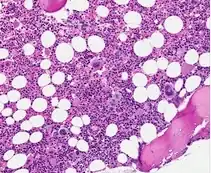

| H&E of bone marrow in grade 0 Prefibrotic PMF | |